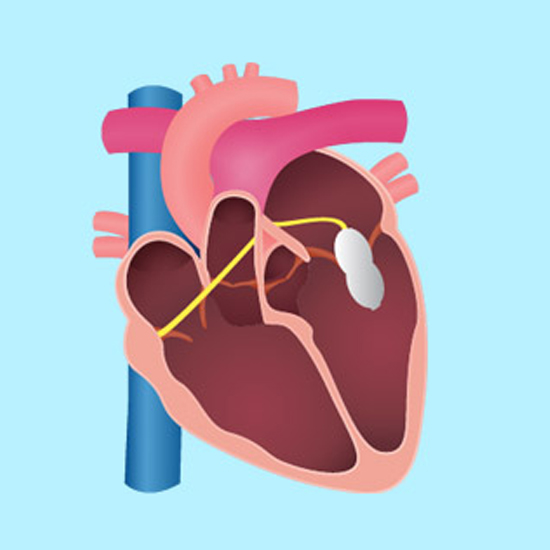

Pacemaker is a small device that's placed in the chest or adbomen to help control abnormal heart rhythms.